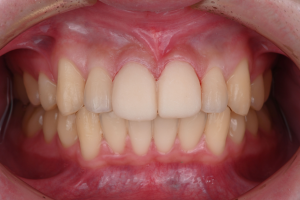

※治療終了時

歯並びが整い、あわせて形にバランスの乱れがあった上の前歯2本は、ラミネートベニアによって自然な見た目に整えられました。

※治療終了時の口腔内写真(正面)

歯科技工士が作製した補綴物は、周囲の歯になじむ自然な見た目に仕上がっています。